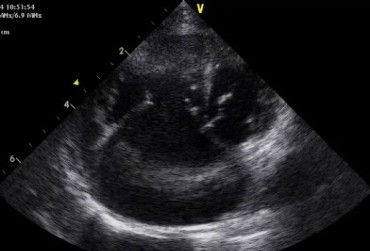

Obraz echo serca przez zabiegiem usunięcia worka osierdziowego 3

19 lutego 2019

Rafał Kraszewski